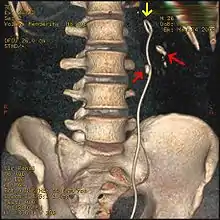

Stones that are large enough to fill out the renal calyces are called staghorn stones and are composed of struvite in a vast majority of cases, which forms only in the presence of urease-forming bacteria. Other forms that can possibly grow to become staghorn stones are those composed of cystine, calcium oxalate monohydrate, and uric acid.[85]

Most stones under 5 mm (0.2 in) pass spontaneously.[32][7] Prompt surgery may, nonetheless, be required in persons with only one working kidney, bilateral obstructing stones, a urinary tract infection and thus, it is presumed, an infected kidney, or intractable pain.[112] Beginning in the mid-1980s, less invasive treatments such as extracorporeal shock wave lithotripsy, ureteroscopy, and percutaneous nephrolithotomy began to replace open surgery as the modalities of choice for the surgical management of urolithiasis.[7] More recently, flexible ureteroscopy has been adapted to facilitate retrograde nephrostomy creation for percutaneous nephrolithotomy. This approach is still under investigation, though early results are favorable.[113] Percutaneous nephrolithotomy or, rarely, anatrophic nephrolithotomy, is the treatment of choice for large or complicated stones (such as calyceal staghorn calculi) or stones that cannot be extracted using less invasive procedures.[56][7]